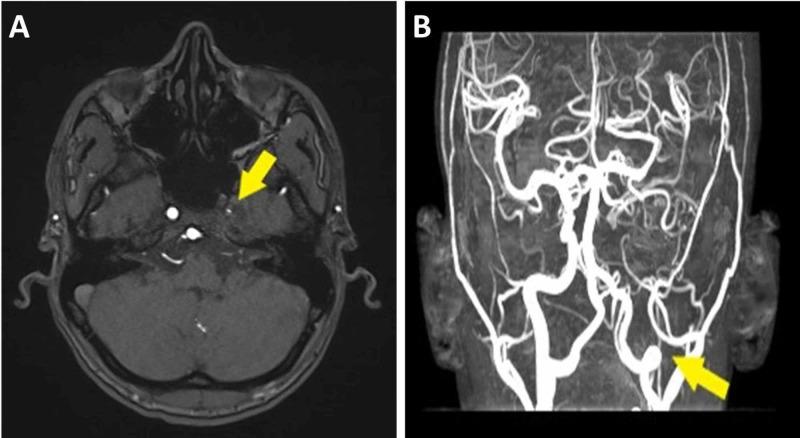

Moyamoya disease (MMD) is an unusual vasculopathy in which the blood vessels of the brain are occluded, resulting in thrombosis. When MMD occurs in association with an underlying pathology, it is known as moyamoya syndrome. The association of moyamoya syndrome with sickle cell disease is uncommon. Herein, we report a case of moyamoya syndrome in a 32-year-old male adult patient.